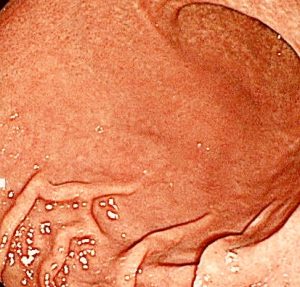

上の写真は、50代男性のピロリ陽性胃炎の写真です。

①胃粘膜の発赤がありますが、襞は多少太い程度で、まだ胃がんのリスクがとても高いとは言えないと思います。